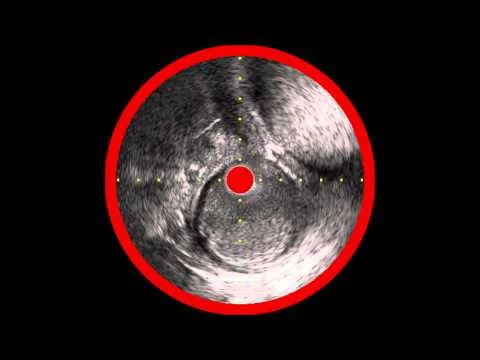

IVUS Distal True Lumen Confirmation of Enteer Re-Entry After Viance CTO Cross